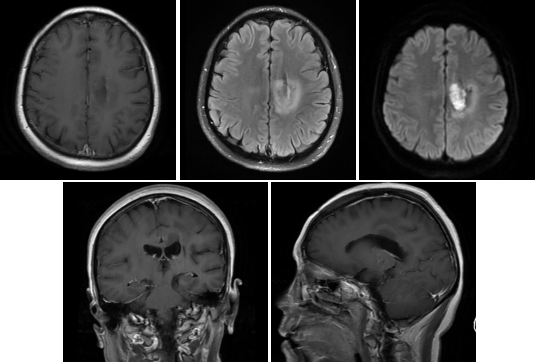

患者1月前无明显诱因下出现右侧肢体麻木无力,右手精细活动障碍,右腿无力,尚可搀扶行走,无头晕头痛,无恶心呕吐,无肢体抽搐等其他不适。遂至外院就诊,行头颅增强MR+MRS检查提示:左侧丘脑异常信号团影,胶质瘤考虑(图1),病灶区Cho/NAA=7.744,NAA/Cr=0.414,提示肿瘤性病变。患者于2周前在外院行病灶穿刺活检术,术后常规病理提示:弥漫性中线胶质瘤,伴H3K27改变,CNS WHO 4级,免疫组化示:GFAP(+),Olig2(+),IDH(-),ATRX(+),P53(+),H3K27M(+),CD34(-),Ki67(30%),H3K27me3(+/-),EMA(-)。近2周来患者右侧肢体麻木无力逐渐加重,并出现言语困难,遂到我院门诊就诊,拟“脑胶质瘤”收住入院。既往无殊。查体:神志清,精神软,言语障碍,语量少,词义性错语,双侧瞳孔等大等圆,直径3mm,对光反应存在,颈软,心肺腹查体未及明显异常,右侧肢体感觉减退,右上肢肌力0级,右下肢肌力III级,左侧肢体肌力V级,右侧Babinski征阳性,左侧阴性。

入院后复查增强磁共振,显示病灶环形强化,瘤内坏死(图2)。完善常规检查及相关检查排除禁忌后,于2023.05.13行磁共振引导下左侧丘脑肿瘤激光间质热疗术(MRgLITT)。